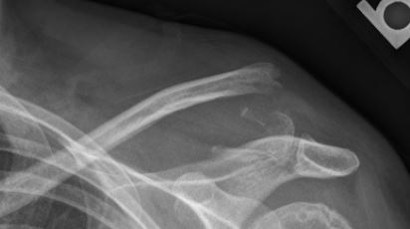

Distal Clavicle Fracture Repair with Buttons

Fracture on the left with the repair on the right.